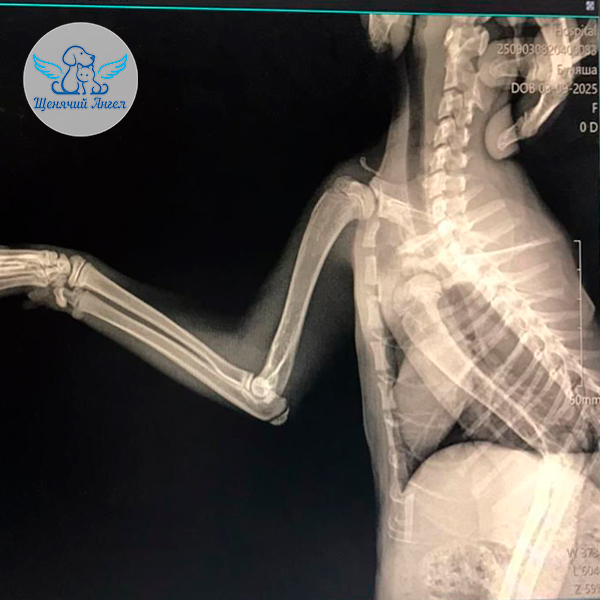

🏥 В ветеринарной клинике города Шахты Буняше провели осмотр и сделали рентген. Перелома, к счастью, не обнаружили, однако травма привела к повреждению нерва 😔. Врачи назначили необходимую терапию, обезболивающие препараты и витамины группы B 💊💉, чтобы попытаться восстановить чувствительность лапки.